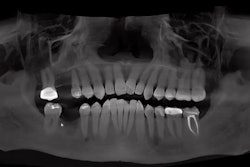

"Now, this patient was referred for removal of fractured teeth #4 and #5 with grafting. Once the patient had healed, we brought the patient back. We got the CEREC scans and we got the cone beam. So let's see how we plan a ghost implant. So the first thing that you do here is you align the crosshairs up right over tooth #3, where the implant had been placed about 10 years ago. And really once that's all set, the next thing that you're going to do is go ahead and set up and place the ghost implant.

"Now why is it a ghost implant? Because I'm putting it directly and perfectly over #3 because I'm going to use this ghost implant on #3 to parallel the implant for #5 so we can have a screw-retained bridge. So once you've got that ghost implant placed, you go ahead and bring the SSI file in like we normally do to bring in the crown proposal for tooth #5.

"Once that's in, you go ahead and you select Implant for #5, and make sure to click Parallel to #3 so it'll make that parallel for the bridge. And once you've done that, you go ahead and bring that virtual implant in for #3, parallel #3 for #5. So once that's done, you go ahead and choose your sleeve and make sure your spacing is correct to do the 360° turn. And then we go ahead.